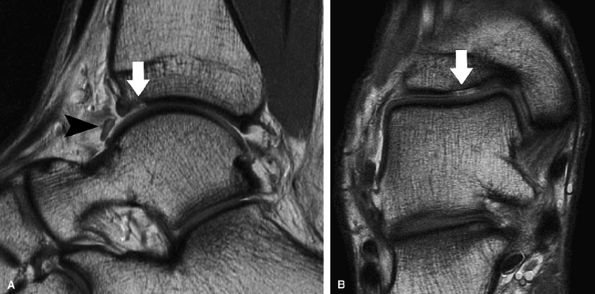

FIGURE 7.21 ● Sagittal (A) and coronal (B) fast spin-echo MR images of the ankle in a 16-year-old patient demonstrate an osteochondral shearing injury (arrows) over the anterior margin of the tibial plafond. A free cartilaginous fragment (arrowhead) in the anterior recess is present. Cartilage over the talar dome is preserved.